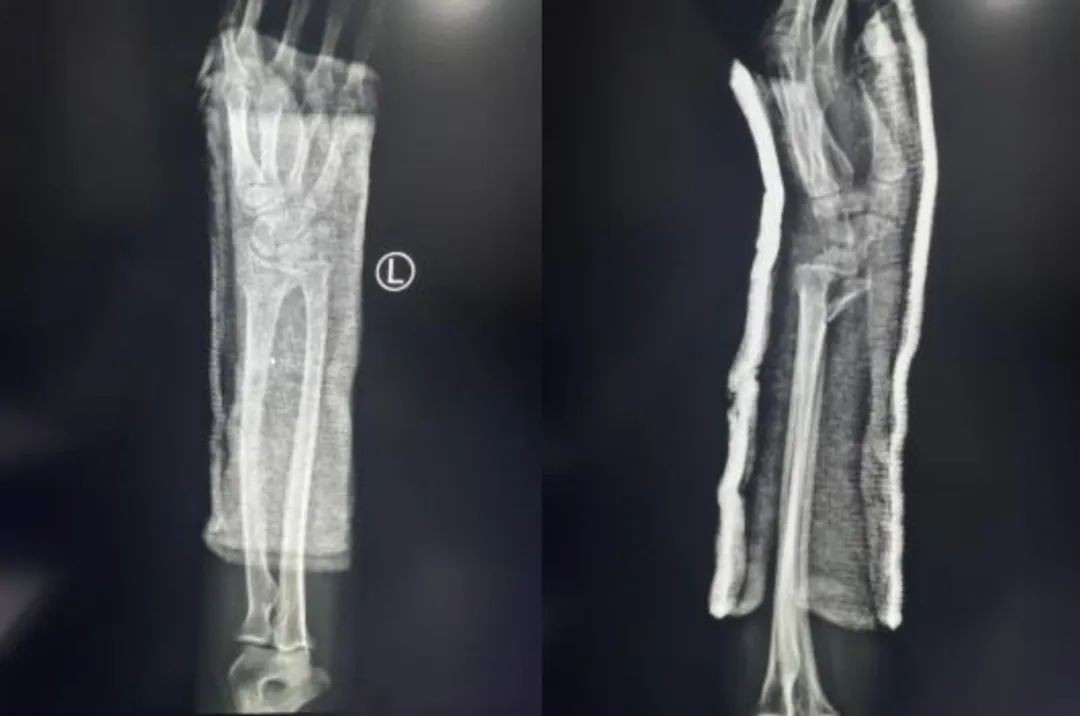

Случай ②